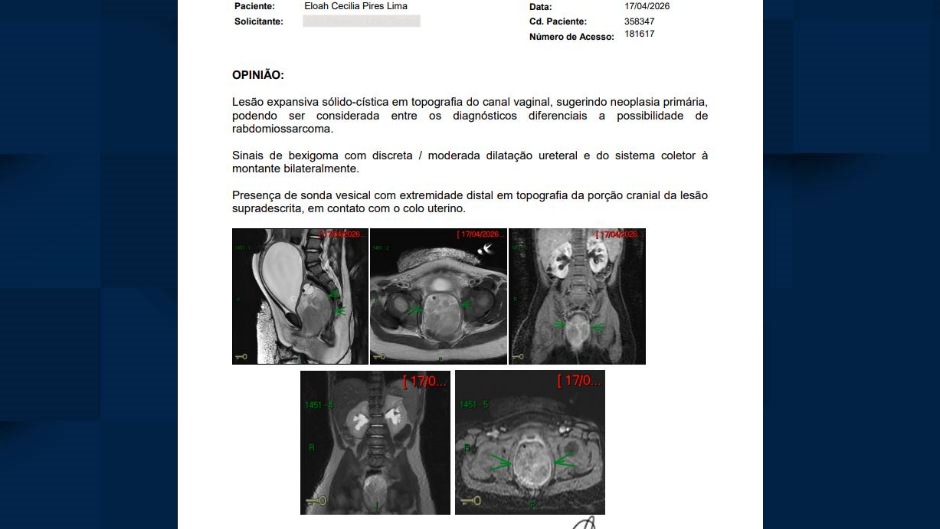

Rafael explica que a filha passou por exames. Por intermédio do hospital, Cecília conseguiu a ressonância magnética que não foi concedida pelo SUS. O exame de imagem confirmou a neoplasia primária, em 17 de abril.

Exame comprova tumor de paciente de dois anos, de Extrema. Imagem cedida pela família.